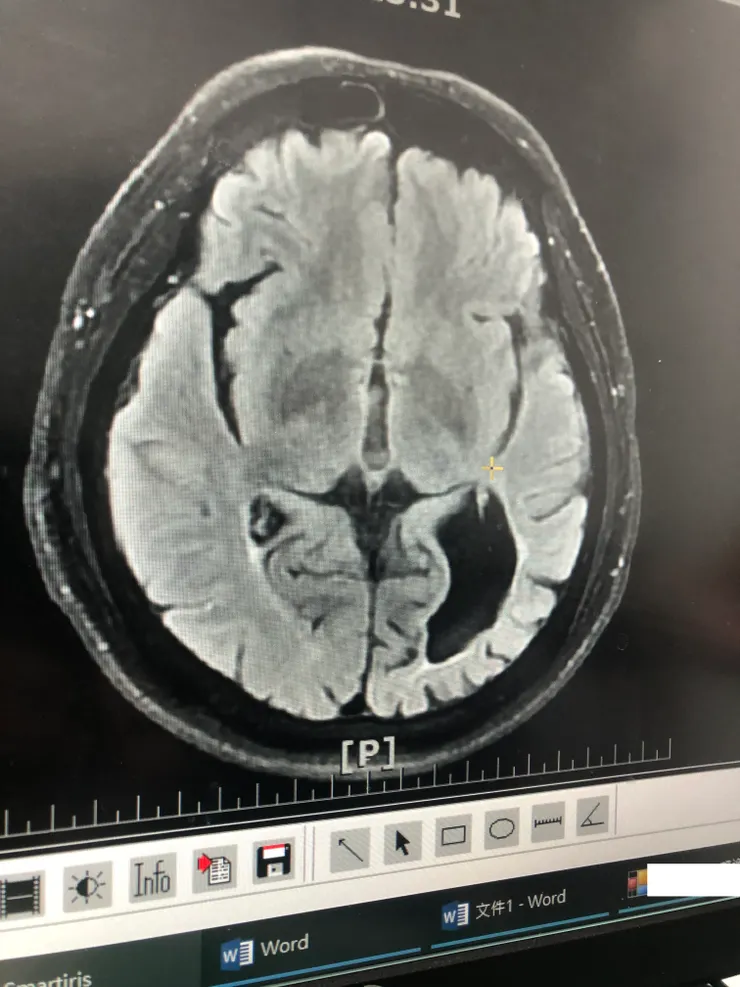

在最近的固定三個月回診拿藥,我有反應最近的一些狀況,神經內科醫師突然要求我再做一次核磁共振,畢竟時間那麼久了,想再確認一下腦內的狀況。

安排好了檢驗的時間,也順利完成了檢查,再次回到門診看報告的時候,造影的結果卻讓我十分震驚。看著電腦上面的影像,心理有很大的震撼,我倒底是闖過了多大的生死關啊~

大腦內部顯影照片,竟然有一個超大的空洞??

腦內缺了一大塊區域...看了挺嚇人的

「腦洞大開」成這樣,而我的思考邏輯、講話幾乎都沒有什麼影響,四肢行動也沒有不便,真不知道是幾輩子修來的福報,過了這麼大一關,人生還能正常繼續。現在只有一些短期記憶問題,還有反應比較慢一點,思考運算有一些影響。